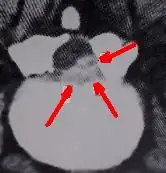

CT scan showing markedly thickened ligamentum flavum (yellow ligament) causing spinal stenosis in the lumbar spine.

Recent studies have shown that cigarette smokers will routinely fail all spinal surgery, if the goal of that surgery is the decrease of pain and impairment. Many surgeons consider smoking to be an absolute contraindication to spinal surgery. Nicotine appears to interfere with bone metabolism through induced calcitonin resistance and decreased osteoblastic function. It may also restrict small blood vessel diameter leading to increased scar formation.[38][39][40][41][42][43][44]